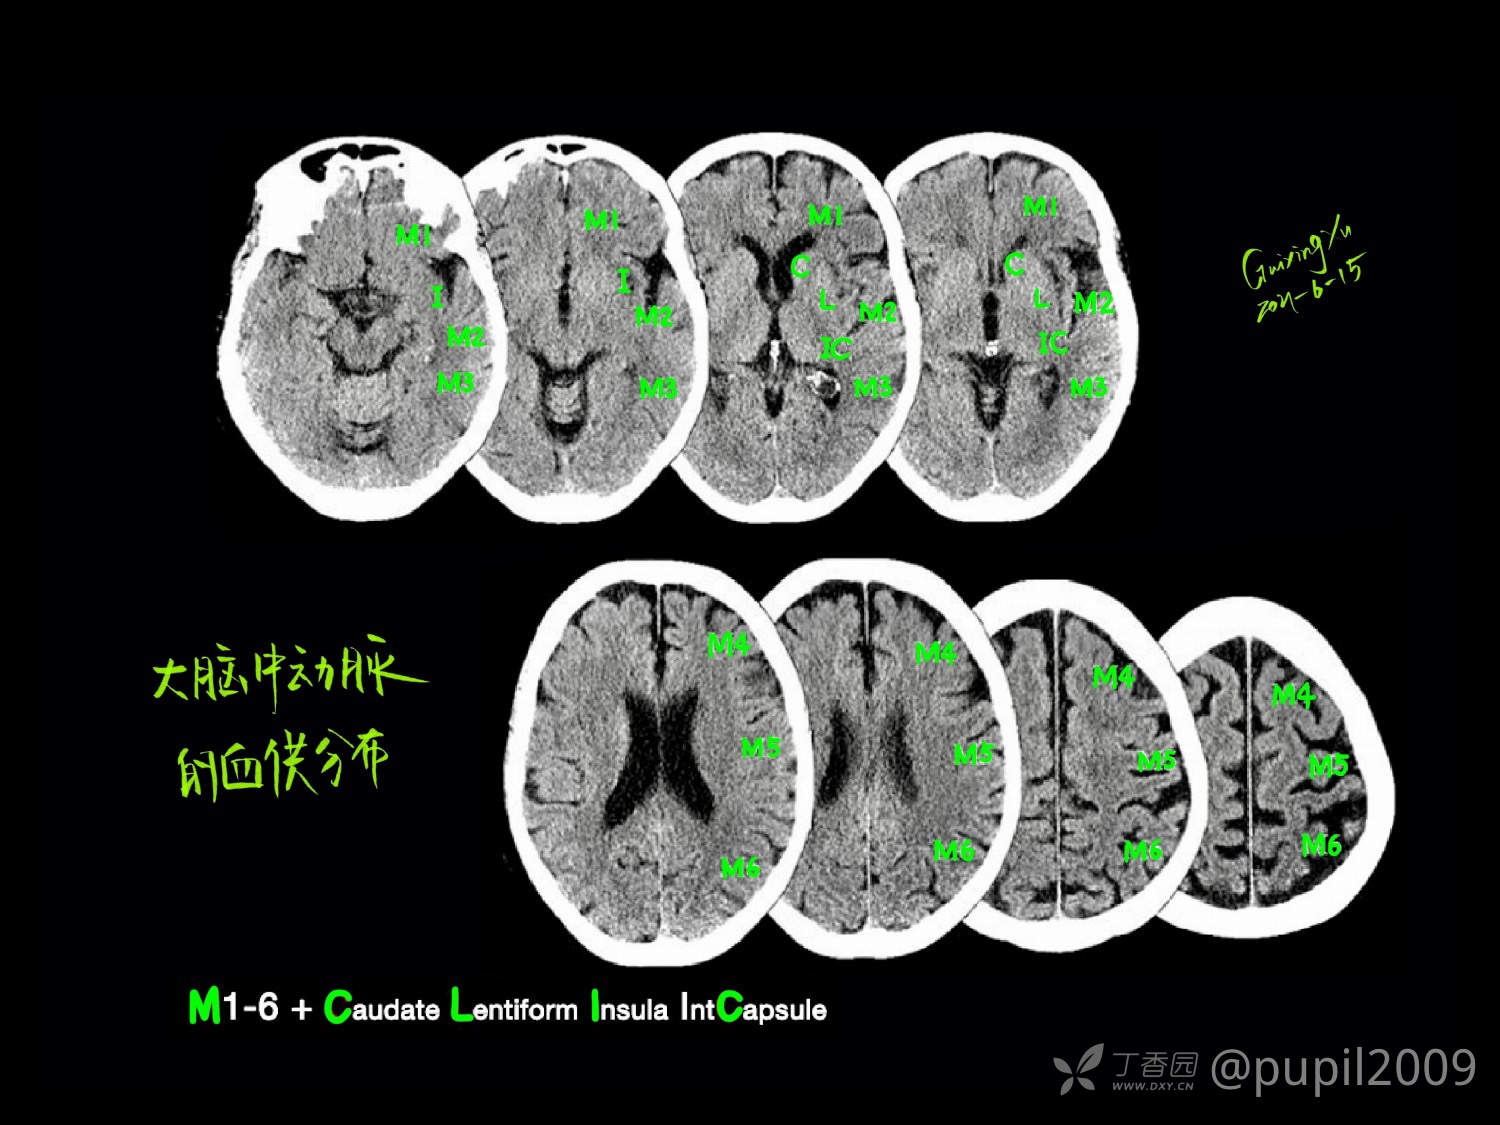

头颅连续断层解剖是通过逐层分析不同平面影像,研究颅骨、脑组织及血管等结构的空间关系,为医学影像诊断和神经外科手术提供精准定位依据。核心在于理解冠状、矢状、水平三个标准切面下的解剖层次,需结合CT、MRI等影像技术掌握关键结构的形态特征。对于医学学习和临床工作,理解头部CT断层解剖是解读影像、诊断疾病的基础。它是影像诊断从“看图”上升到“识病”的必备桥梁。